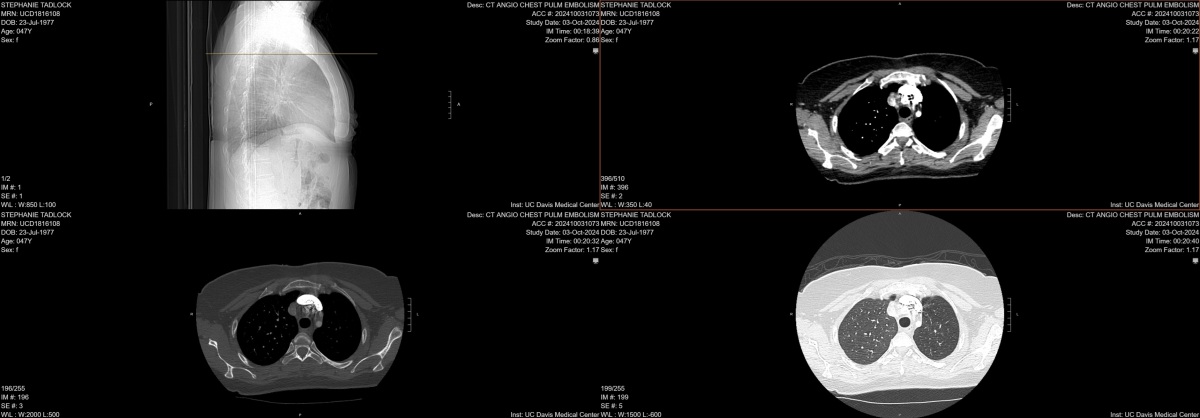

The first scan

This is from the CT scan I got when I went to the ER for the second time for a persistent cough, chest pain, and difficulty breathing. A few hours after this imaging, they told me that they suspected it was cancer.